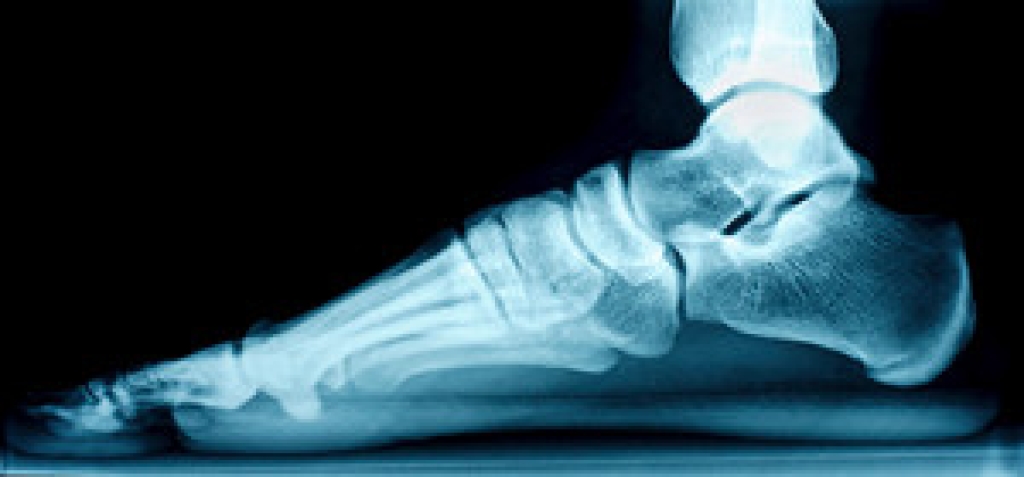

Signs of a Broken Ankle

The ankles play a significant role in balancing the weight of the body and are strong enough to endure participating in strenuous activities. They are also flexible and may be susceptible to breaking, which can happen from landing awkwardly on a hard surface. One of the first signs you may have that you have broken your ankle is severe pain. This is considered to be the body’s natural defense against an injury, and the pain level happens accordingly to the severity of the injury. Other symptoms may include a numbing sensation and immediate swelling, and it is often difficult, if not impossible to walk. A severely broken ankle may have a bone protruding from the skin, which may bleed and become infected. A diagnosis is often performed that can confirm the broken ankle, and treatment can begin. Many people wear a cast or protective boot as their fractured ankle heals, and this may provide an opportunity for mobility. If you have broken your ankle, it is suggested that you confer with a podiatrist who can determine what the best form of treatment is for you.

A broken ankle is experienced when a person fractures their tibia or fibula in the lower leg and ankle area. Both of these bones are attached at the bottom of the leg and combine to form what we know to be our ankle.

When a physician is referring to a break of the ankle, he or she is usually referring to a break in the area where the tibia and fibula are joined to create our ankle joint. Ankles are more prone to fractures because the ankle is an area that suffers a lot of pressure and stress. There are some obvious signs when a person experiences a fractured ankle, and the following symptoms may be present.

Exercises for Flat Feet

Children are naturally born with flat feet, and by the time they are teenagers, the arch usually develops normally. However, there are various circumstances where the arches either do not develop or they fall. These include injuries, obesity, genetics, and arthritis. Those with neurological or muscular diseases may also be more prone to having flat feet. Wearing orthotics or arch supports, and performing certain stretches, can reduce pain from fallen arches or help correct them. Examples of exercises that might help raise, strengthen, and lengthen the arches are heel stretches and tennis or golf ball rolls. Stretch your heels by standing with your hands resting on a wall at eye level. Keep one leg forward and the other extended behind you. Press both heels into the floor. Then bend one leg at a time toward the wall with the opposite heel pressed into the floor and hold this position for 30 seconds. Repeat on each side four times. For the tennis or golf ball roll, sit in a chair with a ball under one foot. Keep a straight spine and roll the ball under your foot, focusing on the arch. Do this for two to three minutes and then change feet. If you have flat feet and they are causing you discomfort, it is suggested that you consult with a podiatrist who can provide you with additional exercise options and further treatment that is right for you.

What Are Flat Feet?

Flatfoot is a condition in which the arch of the foot is depressed and the sole of the foot is almost completely in contact with the ground. About 20-30% of the population generally has flat feet because their arches never formed during growth.